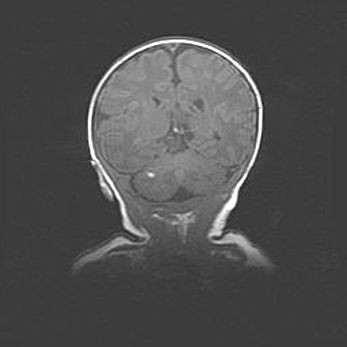

Мальформация Денди-Уокера. Киста задней черепной ямки.

Агенезия мозолистого тела.

Возраст: 2,5 месяца

Вес: 2420 г

Пол: женский

Окружность головы: 37 см

Срок гестации: 32 недели

Мальформация Денди—Уокера — редкий вид патологии ЦНС, представляющий собой врожденный порок развития каудального отдела ствола и червя мозжечка, ведущий к неполному раскрытию срединной (Мажанди) и латеральных (Лушка) апертур IV желудочка мозга. Для этогно синдрома характерна триада симптомов: гипотрофия червя мозжечка и/или полушарий мозжечка, кисты задней черепной ямки, гидроцефалия различной степени. В 70% случаев порок сочетается и с другими аномалиями головного мозга, в частности с агенезией мозолистого тела.